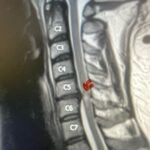

Figs 1a,b: T2-weighted sagittal and axial MRI demonstrating (red arrow) a large right L4-5 foraminal synovial cyst. Note the grade 1 spondylolisthesis (blue arrow)

This 54-year-old female with a long history of low back pain presents with three weeks of a progressive right footdrop with associated numbness and tingling of the right leg. In addition, she had right lateral hip pain down to the dorsum of her foot. She first noticed her right foot slapping the floor when she walked. She had no prior trauma or unusual activity before this began. Her chiropractor, who had treated her back pain for a long time, first noticed the foot drop and referred her for further evaluation. She presented with ⅖ strength in her right dorsiflexor. MRI revealed a large right L4-5 foraminal synovial cyst with some mass-effect on the thecal sac. (Fig. 1) She also had an associated grade 1 spondylolisthesis. Because the cyst was more foraminally-oriented, it had the majority of its effect on the right L4 nerve root. It was felt the patient required surgery to attempt to reverse her weakness. We performed a decompressive laminectomy at L4, removing the inferior facet process on the right in order to gain lateral and foraminal access to the right L4 nerve root. In the lateral recess there was a heap of inflammatory tissue which we entered, revealing the cyst. The medial wall was stuck to the dura. We internally decompressed the cyst which was mainly gelatinous material with some fluid. We dissected and removed as much of the cyst we could safely remove but left the medial wall for fear of removing it would cause a CSF leak, upon removing the bulk of the cyst we encountered anteriorly the descending and exiting right L4 nerve root which was purplish in color and clearly inflamed. We performed a generous foraminotomy of the right L4 as well as the right L5 nerve root. We also performed an instrumented fusion at L4-5 (Fig. 2).